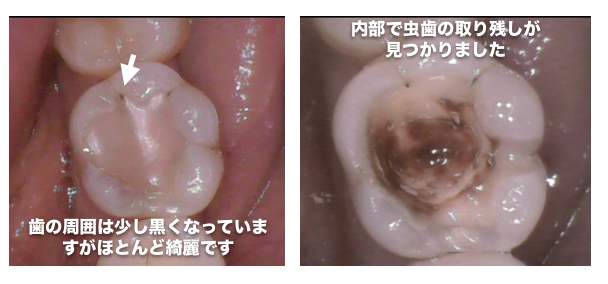

歯を直接見て綺麗なのに内部に透過像があると虫歯の取り残しの可能性があります

CASE9

以前治療したレジン治療の内部から虫歯の取り残しが見つかった症例

レジン治療の内部で虫歯の取り残しがあった症例

虫歯の治療を受ける場合は、患部の写真を撮って治療してもらえる歯科医院に行くことをオススメしています

当院では治療する場合は、口腔内写真を必ず撮影し、治療前と治療中、治療後で最低3枚以上撮影して、 治療後にどのような状態だったのか写真を撮って説明しています

問題が起きている歯や歯茎を口腔内専用カメラで撮影し治療前と治療後を比較。

口腔内写真を取り、患部を拡大することにより、虫歯の取り残しを確実になくししています

当院は虫歯の取り残しがないようにをしっかり治療し、記録を残しています

歯の内部はどのような治療をしているか患者様はわからないため、治療後は自分の目で虫歯の取り残しがないかどうか確認することをオススメしています

上記の写真はここまで虫歯になっていても痛みが全くない症例でした

治療を受ける際は、幹部の写真を撮影している歯科医院をお勧めしています

きちんと虫歯を治療しているかどうかはご自身の目で判断することが重要です